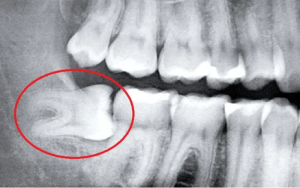

Bác sĩ sẽ sử dụng các thiết bị như chụp X-quang để có cái nhìn rõ ràng về vị trí và tình trạng của răng khôn. Điều này không chỉ giúp xác định răng có mọc lệch hay không mà còn giúp dự đoán các thách thức tiềm ẩn trong quá trình nhổ răng.